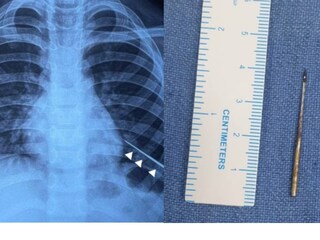

കടുത്ത പനിയും രക്തം ചുമച്ച് ഛർദ്ദിക്കുകയും ചെയ്തതിനെ തുടർന്ന് കുട്ടിയെ ആദ്യം സ്വകാര്യ ആശുപത്രിയിൽ പ്രവേശിപ്പിക്കുകയായിരുന്നു. ഇവിടെ നിന്നാണ് എയിംസിലേക്ക് മാറ്റുന്നത്. എക്സ് റേയിൽ ഇടത് ശ്വാസകോശത്തിൽ സൂചി കണ്ടെത്തി. ശ്വാസകോശത്തിൽ ആഴ്ന്നിറങ്ങിയ നിലയിലായിരുന്നു സൂചിയുണ്ടായിരുന്നത്. ശസ്ത്രക്രിയ ഉപകരണങ്ങൾ ഉപയോഗിച്ച് പുറത്തെടുക്കാൻ സാധിക്കാത്തതിനെ തുടർന്നാണ് കാന്തം ഉപയോഗിച്ചതെന്ന് ഡോക്ടർമാർ പറയുന്നു.

ഇതിനായി ഡൽഹിയിലെ ചാന്ദ്നി ചൗക്കിൽ നിന്ന് 4 mm വീതിയും 1.5 mm കനവുമുള്ള കാന്തം വാങ്ങുകയായിരുന്നു. ഈ കാന്തം ലഭ്യമല്ലായിരുന്നുവെങ്കിലോ, ശ്വാസകോശത്തിൽ സൂചി ദൃശ്യമല്ലായിരുന്നുവെങ്കിലോ കുട്ടിക്ക് തുറന്ന ഹൃദയ ശസ്ത്രക്രിയ നടത്തേണ്ടി വരുമായിരുന്നുവെന്ന് പീഡിയാട്രിക് വിഭാഗത്തിലെ അഡീഷണൽ പ്രൊഫസർ ഡോ. വിശേഷ് ജെയിൻ പറഞ്ഞു.

ശസ്ത്രക്രിയയ്ക്കു ശേഷം കുട്ടി ഡിസ്ചാർജ് ചെയ്ത് മടങ്ങിയതായും ഡോക്ടർ അറിയിച്ചു. ശ്വാസകോശത്തിനുള്ളിൽ വളരെ ആഴത്തിലായിരുന്നു സൂചിയുണ്ടായിരുന്നത്. അതിനാൽ പരമ്പരാഗത ശസ്ത്രക്രിയാ രീതികൾ ഫലപ്രദമല്ലെന്ന് കണ്ടാണ് കാന്തം ഉപയോഗിച്ചതെന്ന് ഡോക്ടർ വിശദീകരിച്ചു. കാന്തം ശ്വാസനാളത്തിലേക്ക് പോകാതെ, സൂചിയുടെ സ്ഥാനത്തേക്ക് എത്തിക്കുക എന്നതായിരുന്നു പ്രധാന വെല്ലുവിളി. നൂലം റബ്ബർ ബാൻഡും ഉപയോഗിച്ച് കാന്തം ഭദ്രമായി ഘടിപ്പിച്ച് പ്രത്യേക ഉപകരണമാണ് ഡോക്ടർമാർ ഇതിനായി കണ്ടെത്തിയത്.

ഇടതു ശ്വാസകോശത്തിനുള്ളിൽ സൂചിയുടെ കൃത്യമായ സ്ഥാനം കണ്ടെത്താൻ എൻഡോസ്കോപി നടത്തി. സൂചിയുടെ അഗ്രഭാഗം മാത്രമേ ഇതുവഴി കാണാൻ സാധിക്കുകയുള്ളൂ. ഇതിനു ശേഷം കാന്തം ഘടിപ്പിച്ച ഉപകരം സൂക്ഷ്മതയോടെ സ്ഥാനത്തേക്ക് കയറ്റി. കാന്തത്തോട് സൂചി പെട്ടെന്ന് അടുക്കുകയും വളരെ വേഗത്തിൽ പുറത്തെടുക്കാൻ സാധിച്ചുവെന്നും ഡോക്ടർ പറഞ്ഞു.